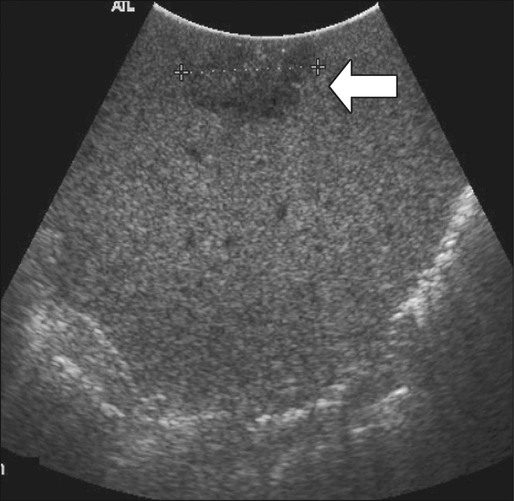

Intraoperative Ultrasound (Open and Laparoscopic)

Intraoperative ultrasound is considered the most sensitive and specific imaging test for detection of hepatic metastases from colon cancer (Fig. 77-15). It is far more sensitive for the detection of metastatic lesions than are inspection and palpation of the liver by the surgeon, particularly for deep tumors.180,181 Liver metastases as small as 3 mm can be detected routinely by intraoperative ultrasound.182 Additional advantages of intraoperative ultrasound are its ability to guide biopsies of suspicious hepatic lesions and its use as an aid in both liver resection planning and guiding tumor ablation (e.g., cryoablation or radiofrequency ablation) (Fig. 77-16). Intraoperative ultrasound has a very limited role in the evaluation of extrahepatic metastases from colon cancer because of the highly targeted nature of the examination. Occasionally, retroperitoneal lymph nodes and other metastatic deposits can be imaged if specific abnormalities are noted on preoperative imaging or if an abnormality is noted during inspection and palpation of the abdomen.

Laparoscopic ultrasound can be used for the same purposes as open intraoperative ultrasound of the liver. Because of lack of access to some areas of the liver, the sensitivity of laparoscopic ultrasound appears to be slightly less than that of open intraoperative ultrasound, but laparoscopic ultrasound has the advantage of being a less invasive approach.183 This approach is particularly useful in patients who have a high likelihood of unresectable liver disease or peritoneal disease or in patients who are to undergo another minimally invasive treatment for known liver metastases, such as tumor ablation.